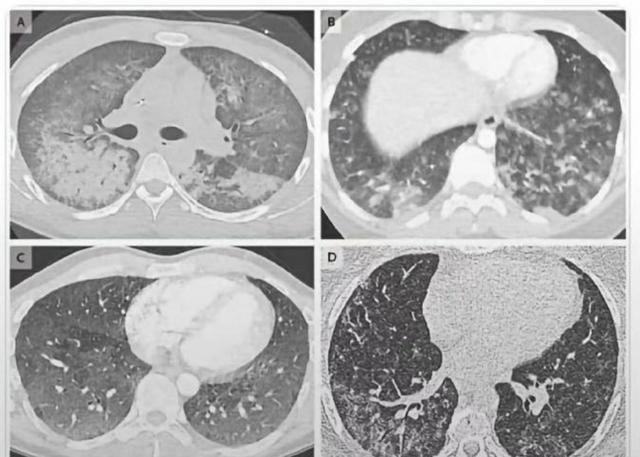

值得注意,早在2019年8月,美国德特里克堡生化基地就已经关闭过一次,当时,美国重点强调,实验室并未发生任何泄露事件。不过很快,美国疾病预防控制中心便宣布,成千上万的人感染了不明原因的肺炎,由于感染者肺部CT图呈现大面积白色且当时没有找到感染原因,该病暂被称为电子烟"白肺病"。并且,由于那一段时间是美国流感季节,因此该传染病的死亡和感染数都被计入美国2019年流感统计。